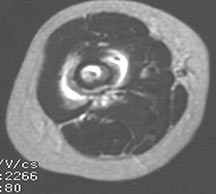

- May arise from any bone and any site within a bone (epiphyseal, metaphyseal, diaphyseal)

- Radiographically variable appearance: may appear benign (geographic) or malignant (permeative or moth eaten)